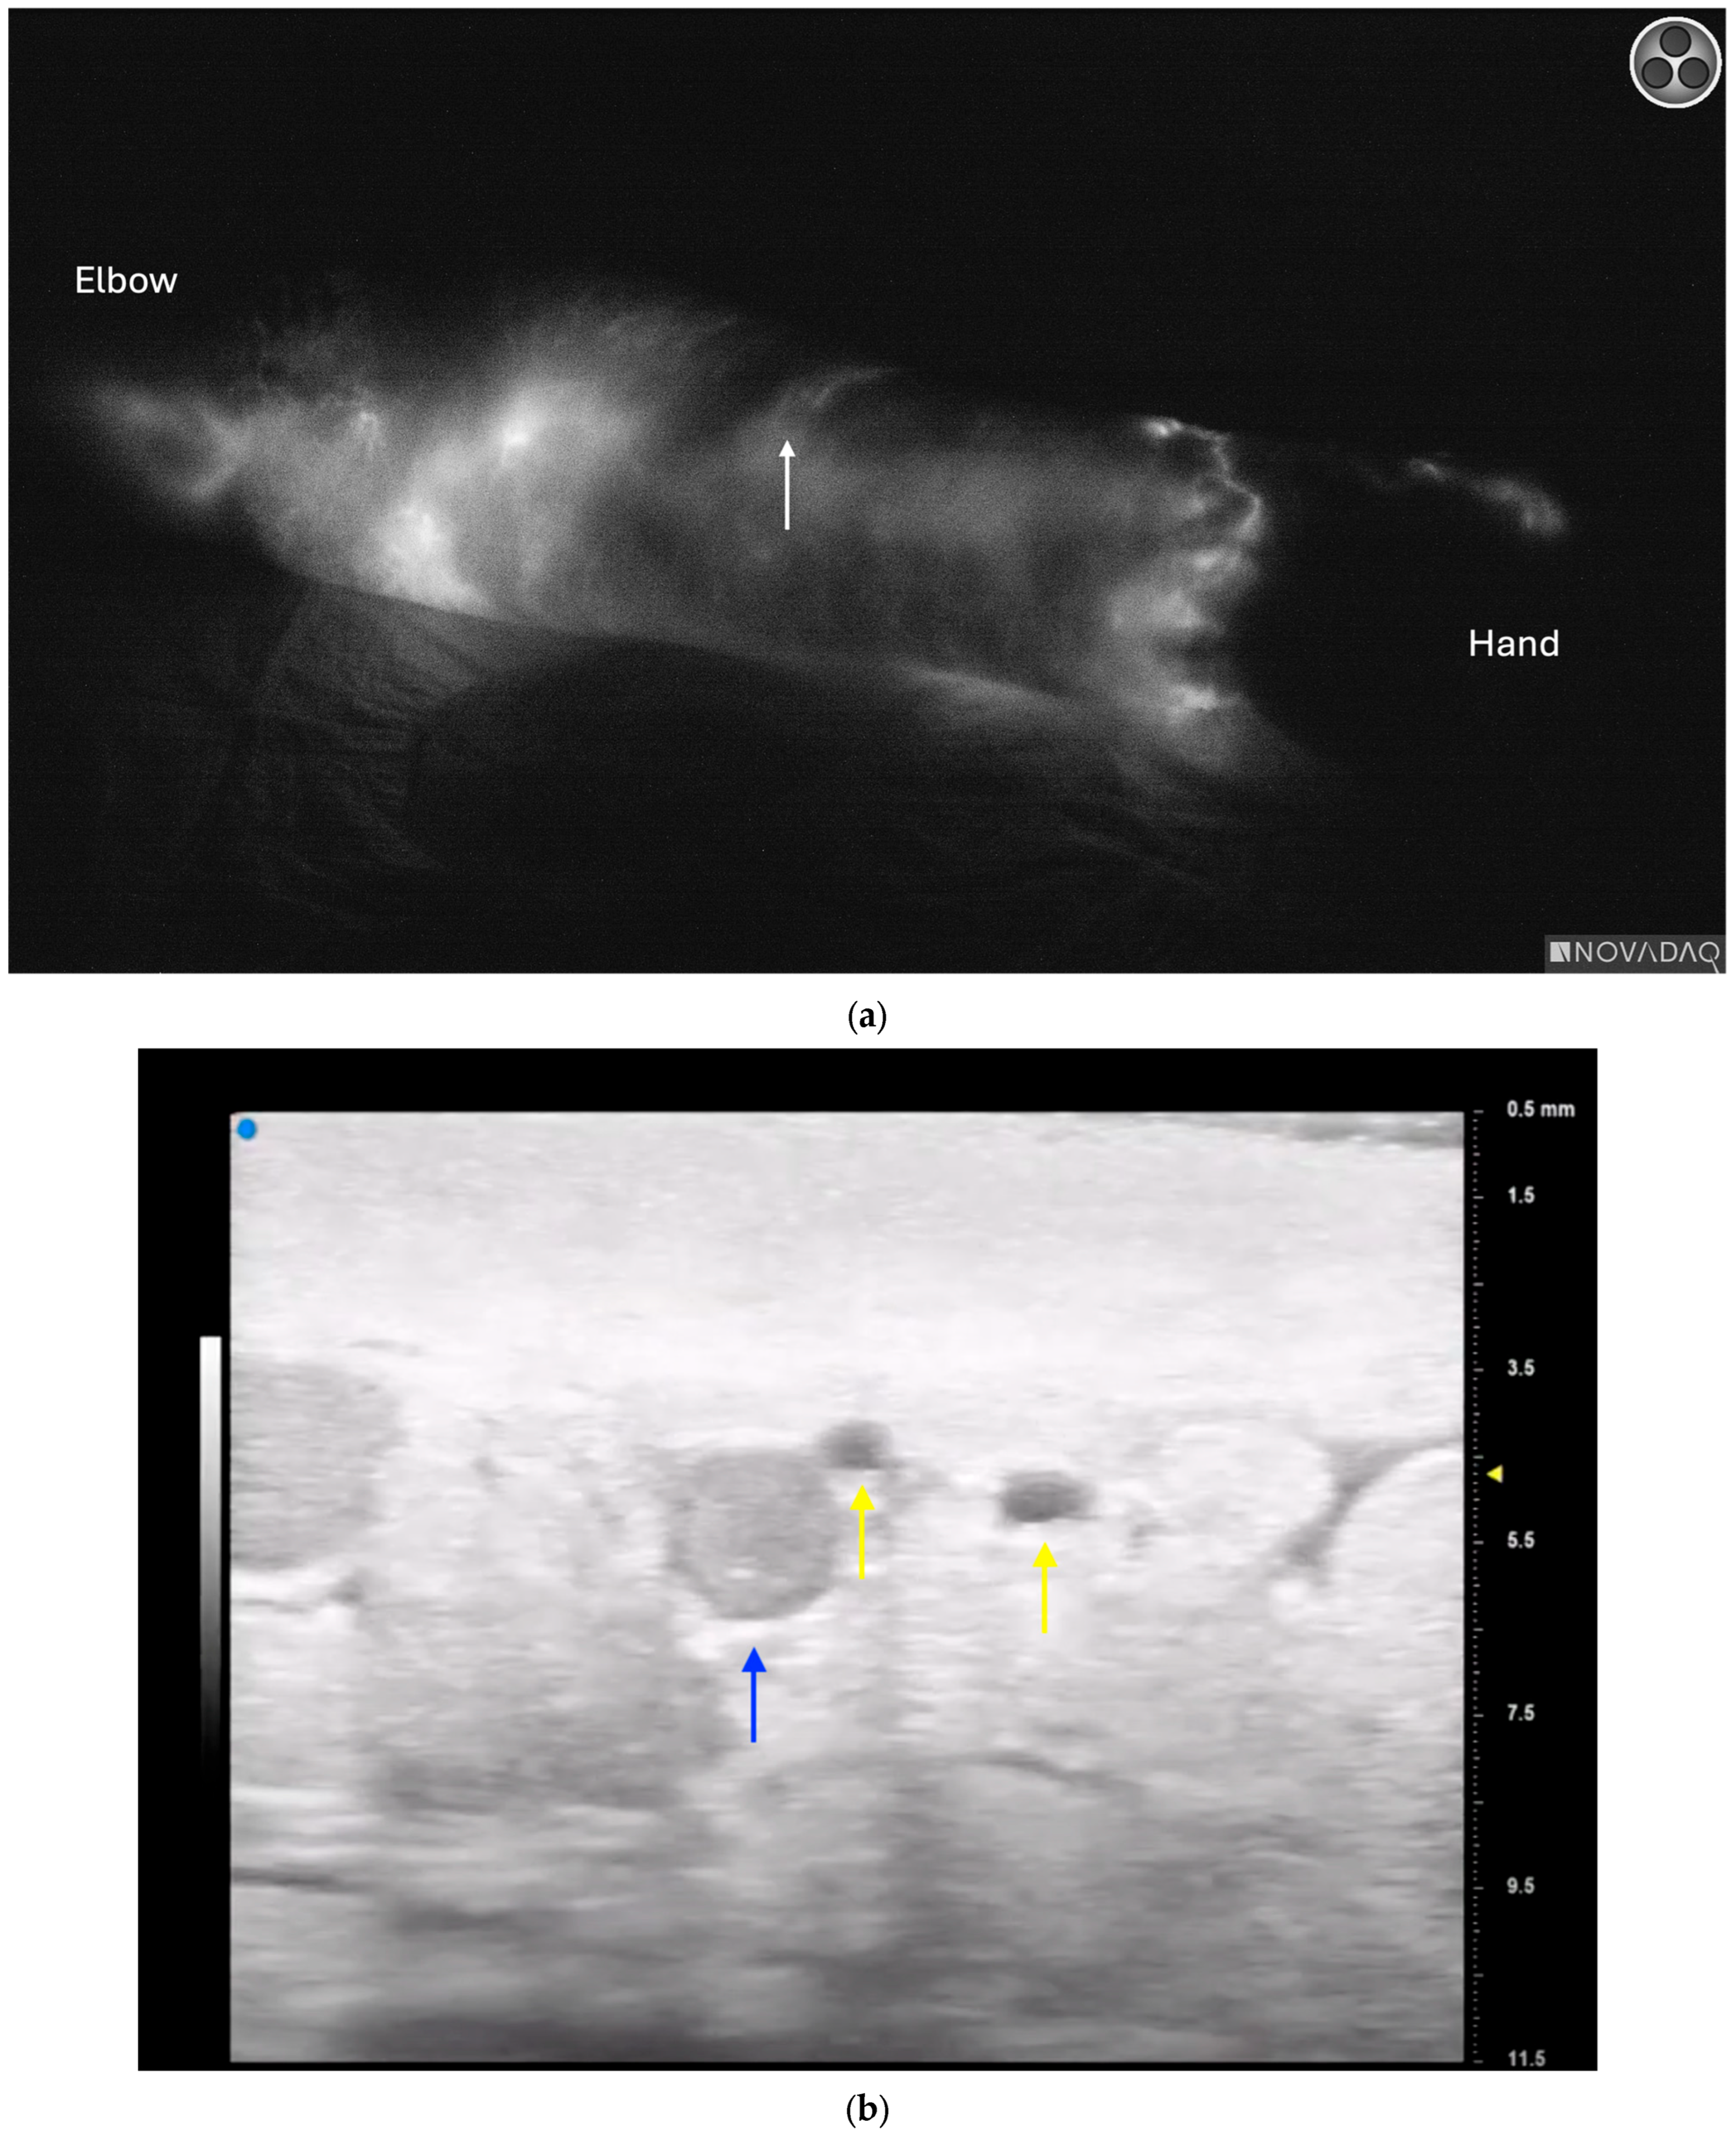

3.4. Lymphatic Surgery

- Hayashi, A.; Giacalone, G.; Yamamoto, T.; Belva, F.; Visconti, G.; Hayashi, N.; Handa, M.; Yoshimatsu, H.; Salgarello, M. Ultra High-frequency Ultrasonographic Imaging with 70 MHz Scanner for Visualization of the Lymphatic Vessels. Plast. Reconstr. Surg.-Glob. Open 2019, 7, e2086. [Google Scholar] [CrossRef] [PubMed]

- Hayashi, A.; Visconti, G.; Giacalone, G.; Hayashi, N.; Yoshimatsu, H. Recent Advances in Ultrasound Technology: Ultra-High Frequency Ultrasound for Reconstructive Supermicrosurgery. J. Reconstr. Microsurg. 2022, 38, 193–199. [Google Scholar] [CrossRef] [PubMed]

- Bianchi, A.; Visconti, G.; Hayashi, A.; Santoro, A.; Longo, V.; Salgarello, M. Ultra-High frequency ultrasound imaging of lymphatic channels correlates with their histological features: A step forward in lymphatic surgery. J. Plast. Reconstr. Aesthetic Surg. 2020, 73, 1622–1629. [Google Scholar] [CrossRef] [PubMed]

- Czedik-Eysenberg, M.; Steinbacher, J.; Obermayer, B.; Yoshimatsu, H.; Hara, H.; Mihara, M.; Tzou, C.J.; Meng, S. Exclusive use of ultrasound for locating optimal LVA sites—A descriptive data analysis. J. Surg. Oncol. 2019, 121, 51–56. [Google Scholar] [CrossRef] [PubMed]

- Seki, Y.; Kajikawa, A.; Yamamoto, T.; Takeuchi, T.; Terashima, T.; Kurogi, N. The dynamic-lymphaticovenular anastomosis method for breast cancer treatment-related lymphedema: Creation of functional lymphaticovenular anastomoses with use of preoperative dynamic ultrasonography. J. Plast. Reconstr. Aesthetic Surg. 2019, 72, 62–70. [Google Scholar] [CrossRef] [PubMed]